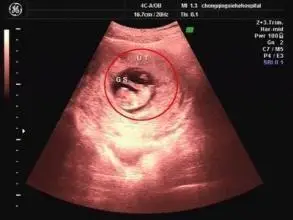

所以孕囊怎么看性别纯属好奇

50天男孩胎囊形状图片如果孕囊大小的长和宽的相差

长孕囊和圆孕囊图片 孕囊一定是男孩的图片

茄子状的孕囊是男孩子?

孕囊看男女性别实例图解附孕囊男孩女孩对照表